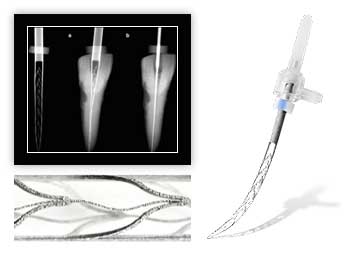

Во время наркоза пациент дышит самостоятельно?

При коротких наркозах пациент дышит сам, при длительных ему помогает дышать аппарат искусственной вентиляции легких.